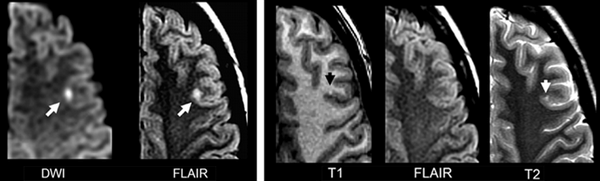

МРТ инсульта и транзиторной ишемической атаки